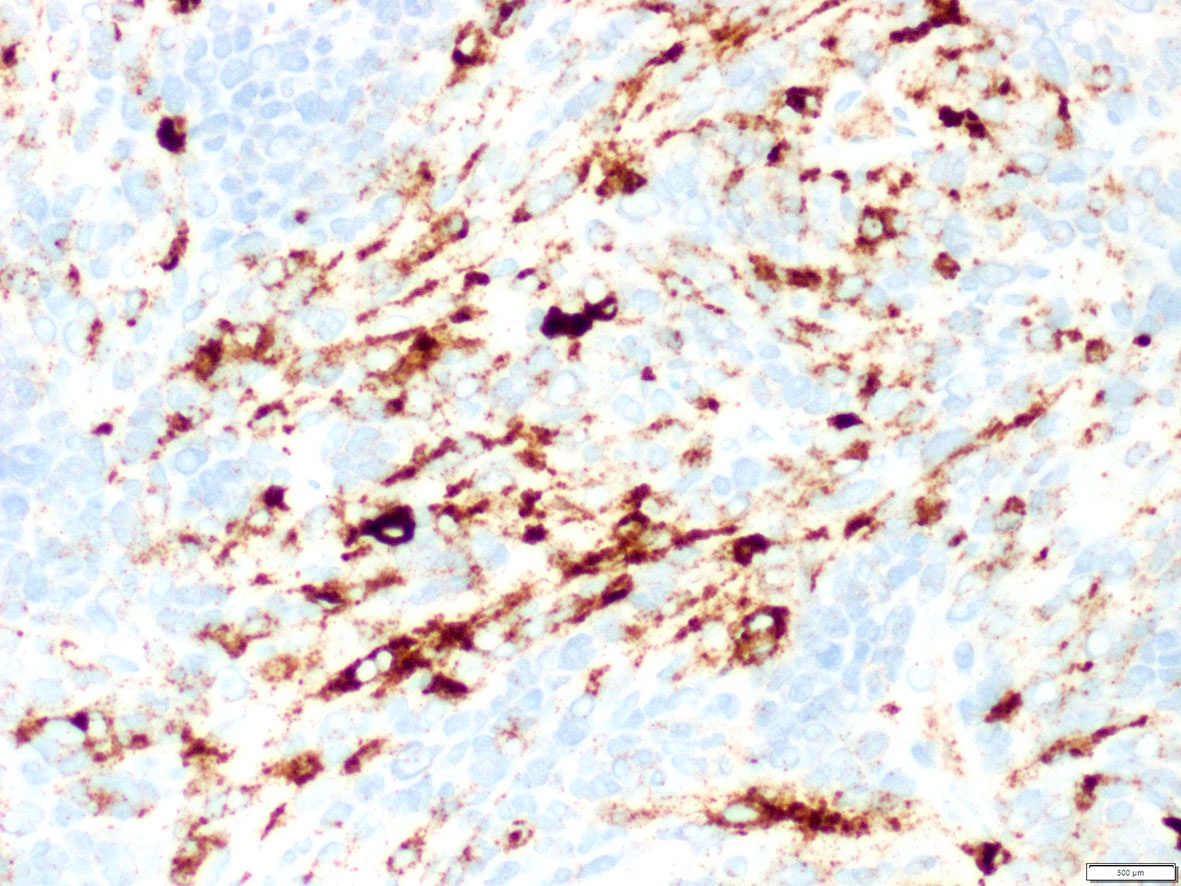

Microscopic (histologic) images

Contributed by A. Cristina Vargas, M.B.B.S., Ph.D., Patricia Guzman, M.D., Fiona Bonar, M.B.B.Ch., Alison Cheah, M.B.B.S. and Martin Jones, M.B.B.S.

Positive staining - disease

- ALK overexpression as a result of gene translocations / fusions:

- Approximately 4% of lung adenocarcinomas, which show an association with mucinous cribriform and solid signet ring cell patterns and usually lack significant pleomorphism (J Clin Pathol 2021 [Epub ahead of print], Am J Surg Pathol 2011;35:1226)

- Pattern of ALK staining varies, depending on the gene fusion partner:

- Diffuse cytoplasmic expression: identified with the following fusion partners: EML4, ATIC, TFG, TPM4, MYH9, ALO17, TRAF1, PABPC1, EEF1G; CLTC-ALK fusion shows cytoplasmic granular / dotted pattern (Semin Diagn Pathol 2020;37:57, Am J Surg Pathol 2017;41:25)